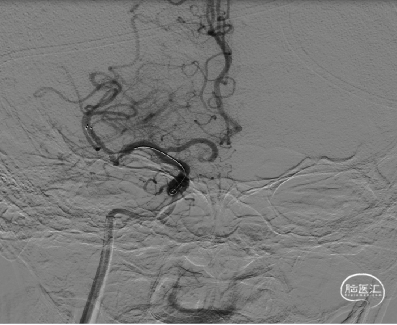

术前造影

右侧颈内动脉闭塞,同时颈外动脉有血栓,闭塞。

右侧颈内动脉起始部呈现“火焰征”,提示假性闭塞,远端眼动脉未见代偿。

前交通开放,左侧A1供应双侧A2。

后交通动脉开放,右侧大脑中动脉可见部分显影。

提示病变为栓塞性串联病变,增加手术难度。这样我们就考虑首先争取单纯抽吸快速开通颈内动脉,然后再SWIM技术取通大脑中动脉。